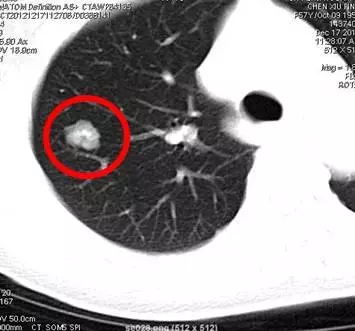

是指肺內(nèi)直徑≤3cm的密度增高影,通俗講就是CT上黑色的肺里有小白點(diǎn)。>3cm的白色塊狀影稱為肺腫塊,通常腫瘤的可能性很大。

結(jié)節(jié)直徑≤3cm

結(jié)節(jié)直徑>3cm